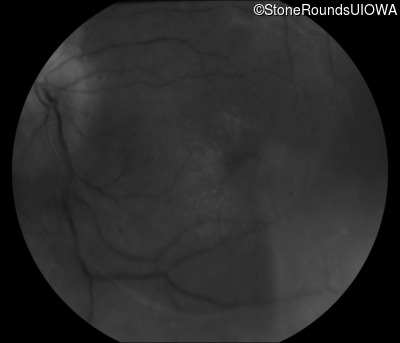

This 43 year old woman first experienced a slight loss of visual acuity at age 23. Fluorescein angiography at that time revealed some vascular leakage from the optic discs and peripheral retina. The maximum combined response of the ERG revealed a selective loss of the b-wave.

Age at visit: 43 years (Visit 2)